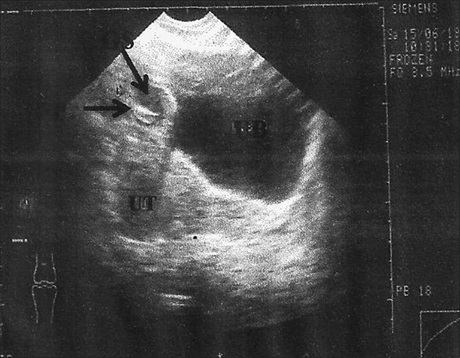

The Utilization of Diagnostic Ultrasound in the Evaluation of the Kidneys in HIV‑Associated Nephropathy

Sani Suleiman Garko, Dr. Philip Oluleke Ibinaiye, Suwaid Moh’d Abba, Ahidjo Ahmed, Sa’ad Suleiman Tanimu, Philip Chinedu Okere (Author)

20-26

Views | PDF/EPUB Downloads : 167 / 23 / 23

DOI: https://doi.org/10.82235/wajr.vol22no1.293